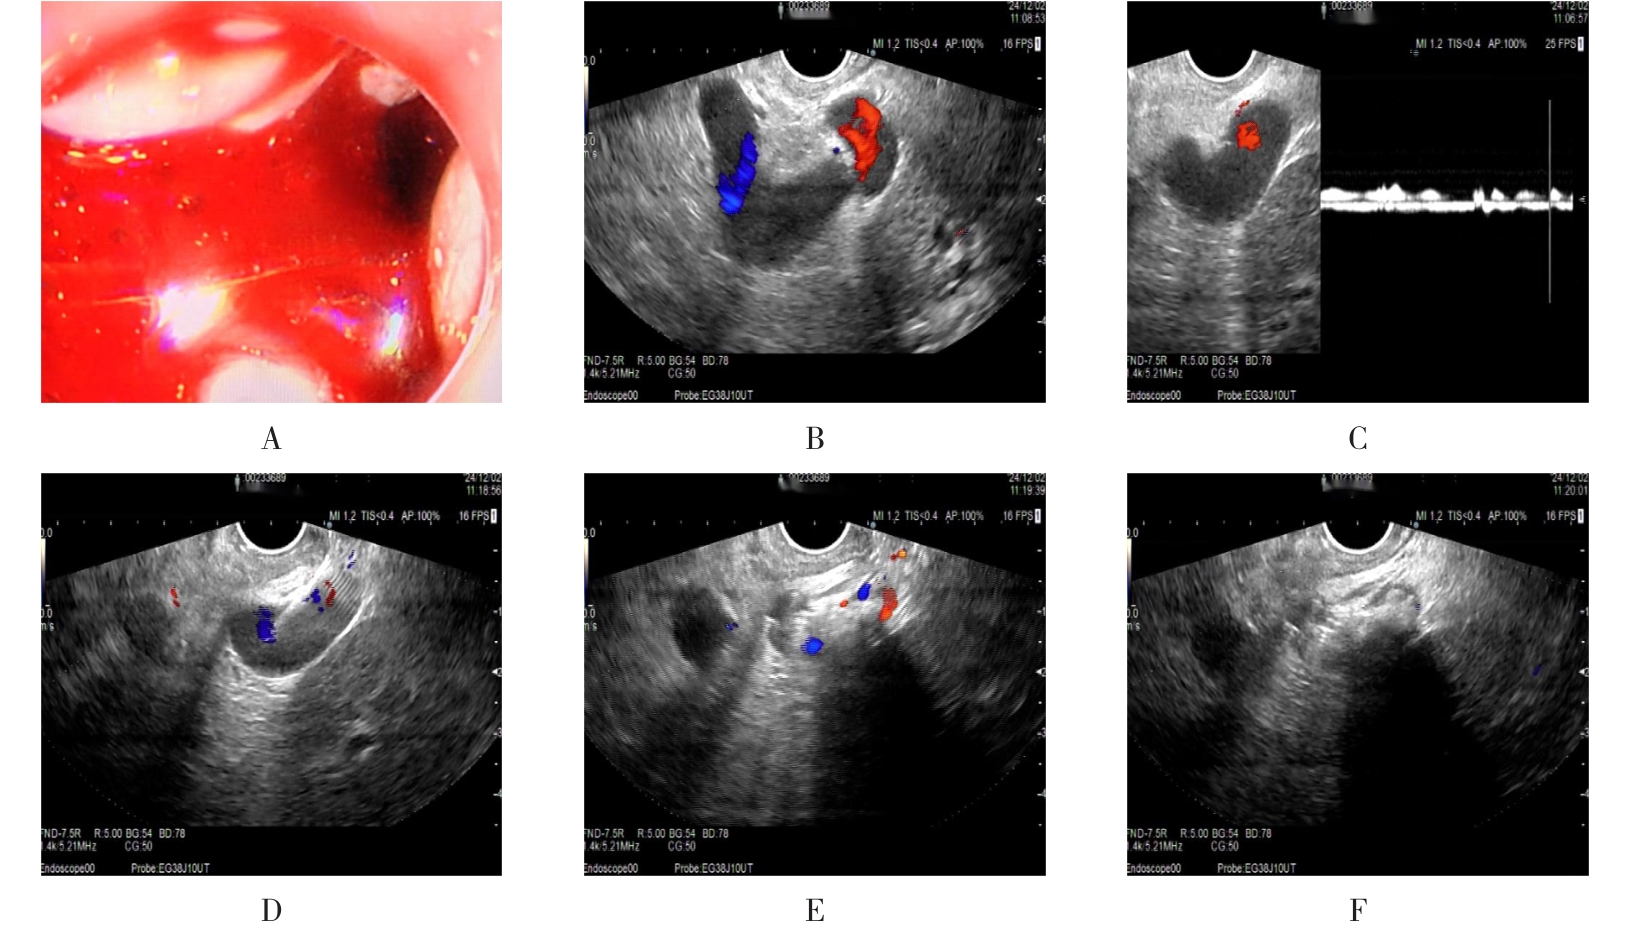

• 超声内镜引导下胃旁曲张静脉精准断流术治疗食管胃静脉曲张出血的疗效分析(附20例报告)

2025, 31(8):85-90. DOI: 10.12235/E20250036

摘要 (153) HTML (42) PDF 5.38 M (98) 评论 (0) 收藏

摘要:目的 探讨超声内镜引导下胃旁曲张静脉精准断流术治疗食管胃静脉曲张出血的疗效。方法 回顾性分析2024年1月1日-2024年12月31日于该院接受超声内镜引导下胃旁曲张静脉精准断流术治疗的20例肝硬化食管胃静脉曲张出血患者的临床资料,并评估治疗效果。结果 20例患者均顺利完成超声内镜引导下胃旁曲张静脉精准断流术;注射组织胶联合置入弹簧圈(16例)和单独注射组织胶(4例)均成功阻断胃旁来源的曲张静脉;所有患者均未发生穿孔、食管贲门狭窄、大出血、败血症和异位栓塞。1例单独注射组织胶的患者,术后胃旁曲张静脉少许渗血,经降低门静脉压力治疗3 d后好转,另1例单独注射组织胶患者,术后出现低热,抗感染3 d后体温恢复正常。结论 超声内镜引导下胃旁曲张静脉精准断流术治疗食管胃静脉曲张出血的临床疗效好,异位栓塞、大出血、感染和穿孔等并发症少,但仍需要密切随访,观察胃旁曲张静脉的排胶问题。